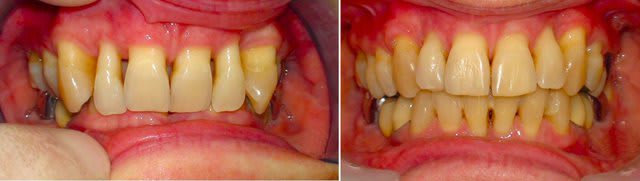

En voici un exemple, c'est un traitement que j'ai réalisé il y a quelques années chez un adulte de 53 ans..

Ce qui est intéressant dans ce cas, c'est que l'ingression s'est accompagnée d'un recul radiculaire des incisives non explicable par la mécanique utilisée (très simple par ailleurs).

Ce que j’ai voulu monter avec le cas d’ingression c’est l’action méconnue de l’orbiculaire des lèvres. Je ne vois pas d’autre explication à ce recul des apex qu’une pression de sa part sur la corticale vestibulaire et un « glissement » de la racine le long de cette corticale.

À rapprocher de l’importante fenestration qu’on peut observer sur son cas à toi.

Ce résultat ne pouvait d’autre part avoir lieu qu’en laissant les dents s’orienter toutes seules et donc en proscrivant tout système traditionnel qui cherche à contrôler les racines. C’est tout l’intérêt des danchamons qui donnent de la liberté aux dents tout en leur indiquant une direction avec des forces très légères, applicables même dans des cas paro très dégradés...